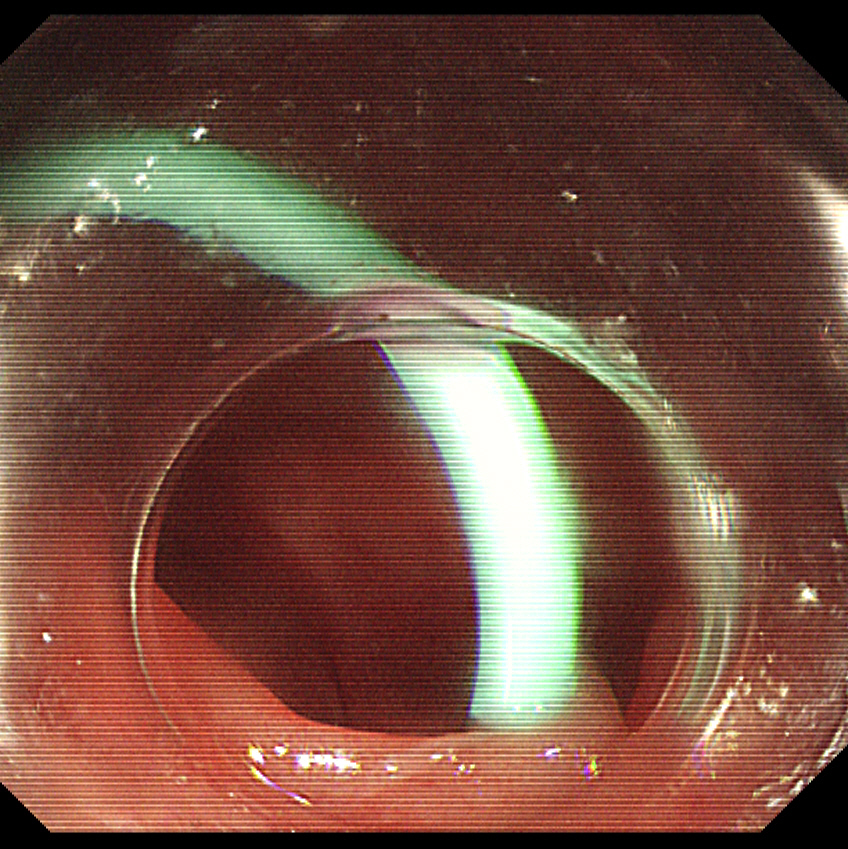

3、洞察系统察看粪石并套取

图片